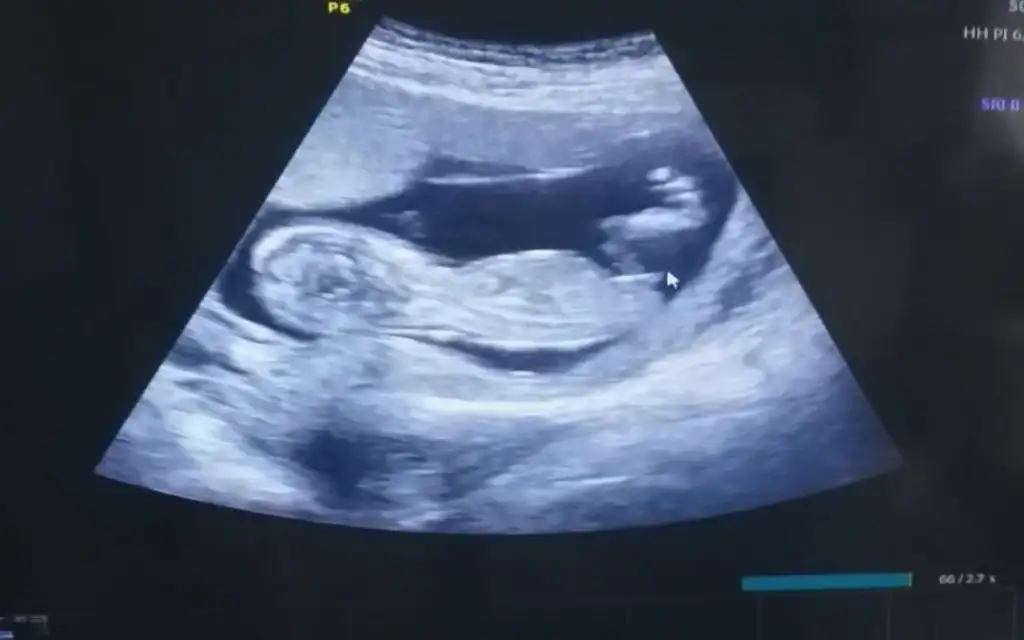

herkes sağolsun gerçekten sıkıldıkça insan buraya giriyor fikir alıyorErkek sankiEki Görüntüle 2807800 Kızlar bizede tahmin de bulunur musunuz

Doktorumuzda çıkıntıya göre erkek gibi ama kordonda olabilir demişti netleşince yazarımErkek sanki

Merhaba, bebeğin cinsiyeti için erkek olabilir demiştiniz ve doğru tahmin etmişsiniz. Tahmininiz için teşekkür ediyorum :)En iyi 11 12 13 haftalar olmalı